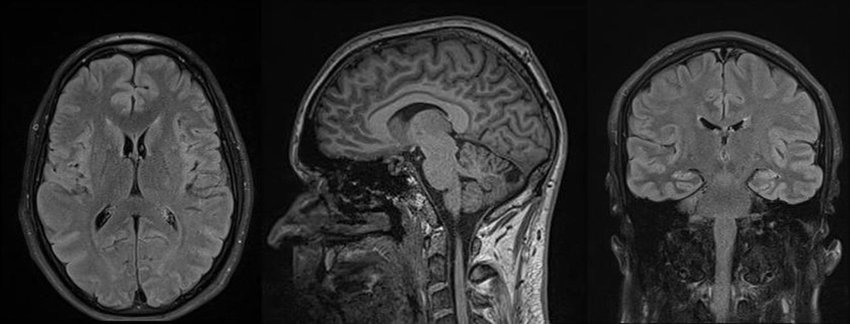

Beynin manyetik rezonans görüntülemesi yani beyin mr beyninizin ve beyin sapınızın ayrıntılı görüntülerini üreten ağrısız, invazif olmayan bir görüntüleme yöntemidir. MR cihazı, görüntüleri manyetik alan ve radyo dalgaları kullanarak oluşturur. Bu MR çekimi aynı zamanda kranial MR olarak da bilinir. Beyin MR’ı çekmek için bir hastaneye veya radyoloji merkezine gideceksiniz.

MR çekimi, görüntü oluşturmak için radyasyon kullanmaması bakımından BT çekiminden veya röntgenden farklıdır. MR çekimi, beyin yapılarınızın 3 boyutlu görüntülerini oluşturur. Bu nedenle, hipofiz bezi ve beyin sapı gibi beynin küçük yapılarındaki anormallikleri tespit etmede diğer görüntüleme yöntemlerinden daha etkilidir. Bazen belirli yapıları veya anormallikleri daha iyi görüntülemek için intravenöz (IV) bir kanülden kontrast madde verilebilir.

Beynin yapısı ve işleyişi, manyetik rezonans görüntüleme (MR) taraması aracılığıyla incelenir. Çeşitli nörolojik ve nörocerrahi durumların tanısını koymak, izlemek ve değerlendirmek için beyin magnetik rezonans (MRI) taramaları yaygın olarak kullanılır. Bazı durumlar beyin MR taraması yoluyla belirlenebilir: